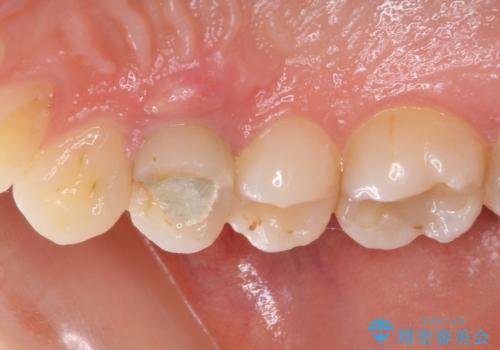

深い虫歯の歯を抜歯 目立つ小臼歯のインプラント治療

- 他院で抜歯が必要と診断され、インプラント治療を希望して来院された患者様です。

口を開けたときに目に付く領域であったので、ジルコニアカスタムアバットメントを用いたインプラント治療を行うこととしました。

ジルコニアカスタムアバットメントは、歯肉ラインに金属が見えにくいというだけでなく、クラウンを装着する土台の形が天然歯と近い形態となるため、清掃性が高く歯肉が腫れにくいというメリットがあります。